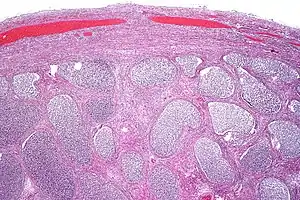

| Acute epididymitis with abundant fibrinopurulent exudate in the tubules. | |